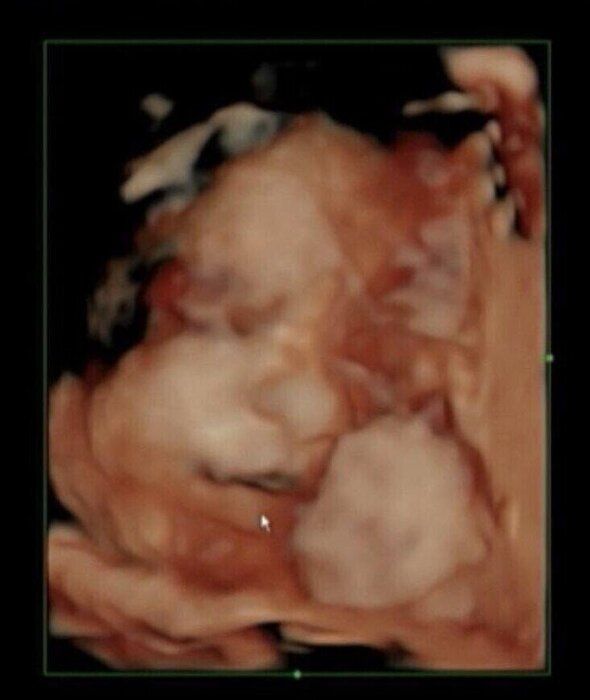

初めて妊娠した人の多くは、妊娠18~20週ごろから、胎動を感じるようになります。おなかの赤ちゃんはもっと早い時期から動いているのですが、このころから動きがさらに活発になり、ママに伝わるようになります。

胎動の感じやすさは個人差が大きく、ママの体形や赤ちゃんの位置、ママの姿勢や時間帯でも違ってきます。胎動がなかなか感じられないとしても、健診の際の超音波検査で赤ちゃんの元気な姿が確認できていれば心配ありません。